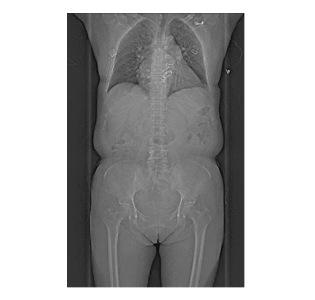

搭載Cinematic VRT三維重建技術(shù),立體還原器官、全身大血管解剖結(jié)構(gòu),對(duì)血管狹窄、斑塊性質(zhì)一目了然。 智能分析組織灌注(心肌/腦/肺),提升診斷效率與準(zhǔn)確性。

1.心腦血管疾?。?.14秒完成心臟掃描,冠脈成像不受心率限制,也同時(shí)支持心肌灌注評(píng)估。 2.腫瘤診療:雙能量技術(shù)助力良惡性鑒別、療效監(jiān)測(cè),實(shí)現(xiàn)腫瘤體積、密度的動(dòng)態(tài)追蹤。3.神經(jīng)系統(tǒng)檢查:對(duì)于腦外傷、出血、腫瘤等疾病的診斷,可提供高質(zhì)量的圖像,幫助醫(yī)生準(zhǔn)確判斷病情。雙能量活動(dòng)性腦出血分析和神經(jīng)灌注檢查,有助于評(píng)估腦卒中缺血半暗帶,為臨床治療決策提供重要參考。 4.急診與重癥:1秒全身成像快速排查多發(fā)傷、肺栓塞等急危重癥,縮短檢查時(shí)間。

檢查無(wú)需藥物控制心率或長(zhǎng)時(shí)間準(zhǔn)備,減少等待焦慮。80cm超大掃描范圍,肥胖或特殊體位患者亦可輕松完成檢查。